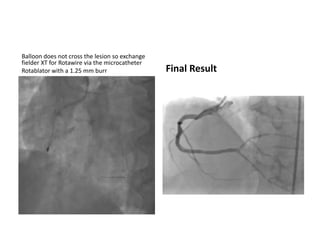

Balloon does not cross the lesion so exchange

Rotablator with a 1.25 mm burr Final Result

Balloon does notcross the lesion so exchange fielder XT for Rotawire via the microcatheter Rotablator with a 1.25 mm burr Final Result